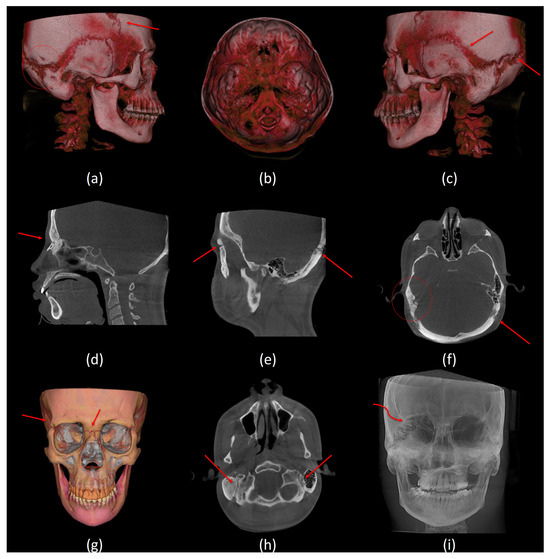

Figure 3.

Sutures and other radiographic features. (a) A lateral view of 3D volumetric rendering shows delayed fusion of the coronal suture and Wormian bone at the occipital–mastoid region, (b) top view of 3D volumetric rendering shows copper beaten appearance, (c) a lateral view of 3D volumetric rendering shows delayed fusion of the squamous and lambdoid sutures, (d) a mid-sagittal CBCT slice shows delayed fusion of the frontonasal suture, (e) a sagittal CBCT slice shows delayed fusion of the frontozygomatic and lambdoid sutures, (f) an axial CBCT slice shows wormian bone on the right and delayed fusion of the lambdoid suture on the left, (g) a frontal view of 3D segmentation model shows delayed fusion of the right frontozygomatic suture and the frontonasal suture, (h) an axial CBCT slice shows delayed fusion of the occipitomastoid sutures, and (i) a frontal view of maximum intensity projection (MIP) shows delayed fusion of the right aspect of the lambdoid suture.

Delayed fusion of the cranial sutures was a prominent characteristic in our sample. This was observed in the lambdoid, occipto-mastoid, squamous, coronal, fronto-zygomatic, and fronto-nasal sutures. Only one subject showed persistent spheno-occipital synchondrosis. Wormian bones were present in all six subjects. Four out of the six subjects had a brachycephalic skull shape with a thinned diploe. Cervical spine abnormalities, such as reduced intervertebral joint space and reduced atlantooccipital joint, were recorded in the DS group. One subject had an anticlockwise-rotated C1 vertebra, accompanied by clockwise-rotated C2 and C3 vertebrae, which represented the most severe anomaly in our sample (Figure 4h). Table 5 provides a summary of the dental and craniofacial features of the six DS cases using Cone Beam Computed Tomography (CBCT).